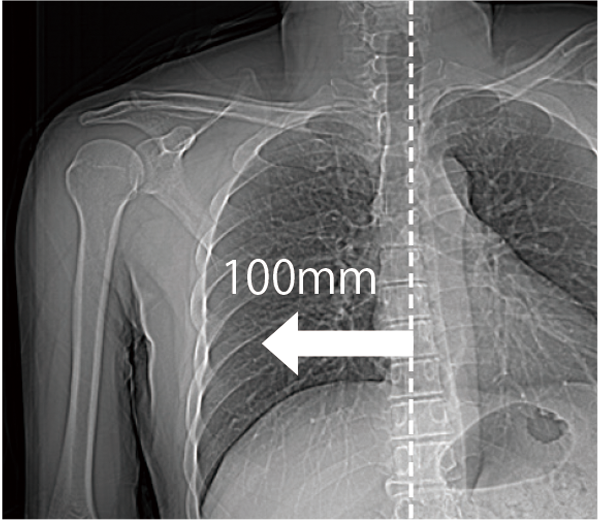

The patient table can move horizontally up to 200 mm, making it easier to position the scanned region in the center, even in cardiac or orthopedic areas, such as the shoulder. This is expected to improve examination efficiency.

Positioning the heart near the center of the field of view